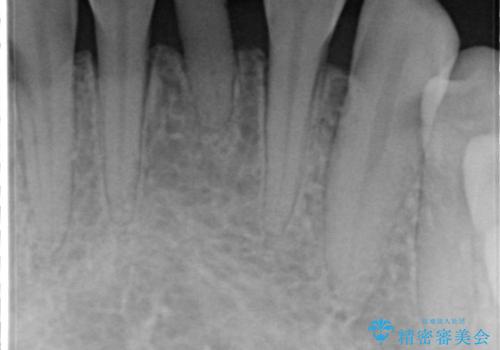

- 晩期残存した下顎乳中切歯の変色を主訴に来院されました。

後続永久歯は先天性欠如しており、下顎前歯のブリッジにて補綴治療を行なっております。